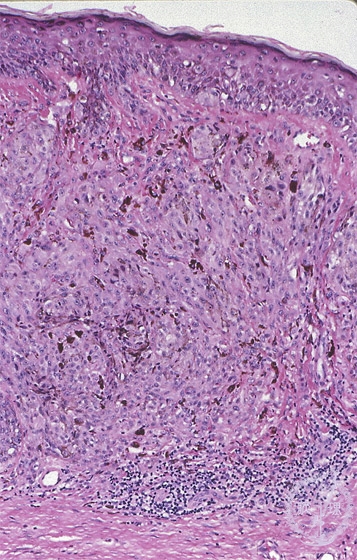

- ★(10)Malignant melanoma

Microscopic findings: Primary lesions show intraepidermal spread. Tumor cells usually have melanin pigments which is reflected in a macroscopic black color. Characteristic of these lesions and different from benign melanocytic nevus melanin pigmentation is also seen in the deep (distal to skin surface) area.